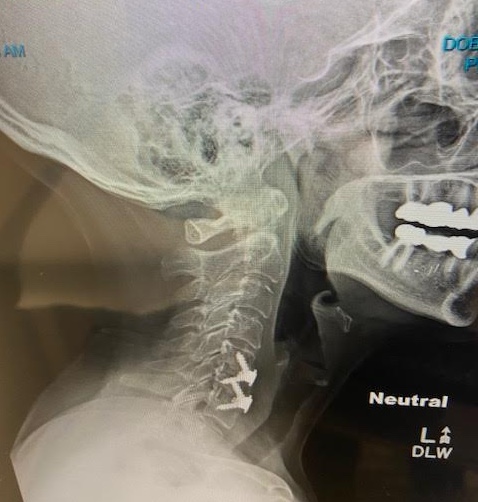

My mother always told me my fondness for chocolate would come back to haunt me someday. And boy am I glad she’s no longer with us, because she would certainly gloat and give me that that “I told you so!” look if she knew I underwent two root canal procedures within a matter of weeks. The hours I spent in the dentist’s chair were worsened by the fact that I carry a bunch of metal in my neck, primarily the result of all those years I participated in sports. (Remember when they told us sports were good for us? They lied!)

A short time after the second root canal, my surgically repaired neck took offense. A spasm ignited, slamming into my left jaw, and no amount of Tylenol, gummies, or sweet dark rum would touch the pain. Not even my trusty heating pad provided any relief. So, I rushed off to my favorite masseur. Wayne McCallum poked and prodded and a short time later, all that pain stopped. I’m still thinking about nominating him for the sainthood, because there’s nothing better than feeling good again.